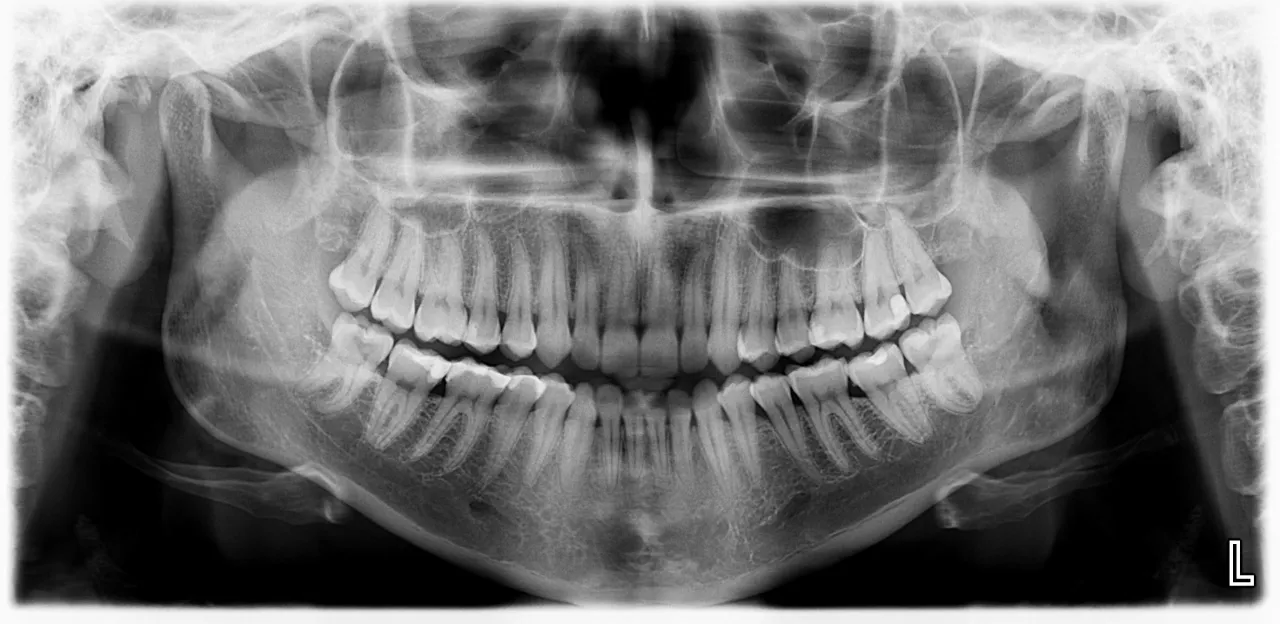

W przypadku zaawansowanej diagnostyki stomatologicznej, takiej jak wykonanie pantomogramu (panoramicznego zdjęcia rentgenowskiego całej szczęki i żuchwy) czy innych zdjęć rentgenowskich zęba w ramach NFZ, konieczne jest skierowanie. Dokument ten musi być wystawiony przez lekarza dentystę. Bez skierowania nie będziesz mógł skorzystać z tych badań w placówkach, które mają umowę z NFZ. To ważne, ponieważ pantomogram dostarcza kluczowych informacji o stanie uzębienia, kości i zatok, niezbędnych do planowania leczenia.